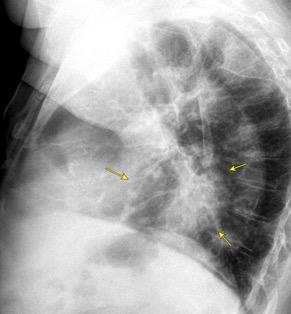

0,4% de casos de trauma. 80% lado izquierdo. Bilateral. 3%

Penetrante..63% 20-59%. Arma de fuego 15-32%. Arma blanca

Trauma cerrado. 37%

Tráfico Caída de gran altura

Aplastamiento toracoabdominal

Furak J et al. Diaphragm and transdiaphragmatic injuries. J Thorac Dis 2019

Accidente de tráfico

Rx: Niveles hidroaéreos en hemitórax izquierdo Desviación mediastínica Ausencia de intestino en abdomen. Configuración en reloj de arena del intestino herniado “Tubo nasogástrico”